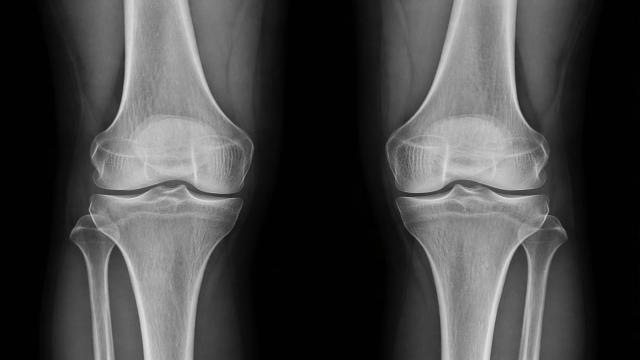

Исследователи из Стэнфордского университета сделали важный шаг к созданию методов лечения остеоартрита — распространенного заболевания, которое ограничивает подвижность и вызывает хроническую боль у пожилых людей. В ходе экспериментов на мышах…